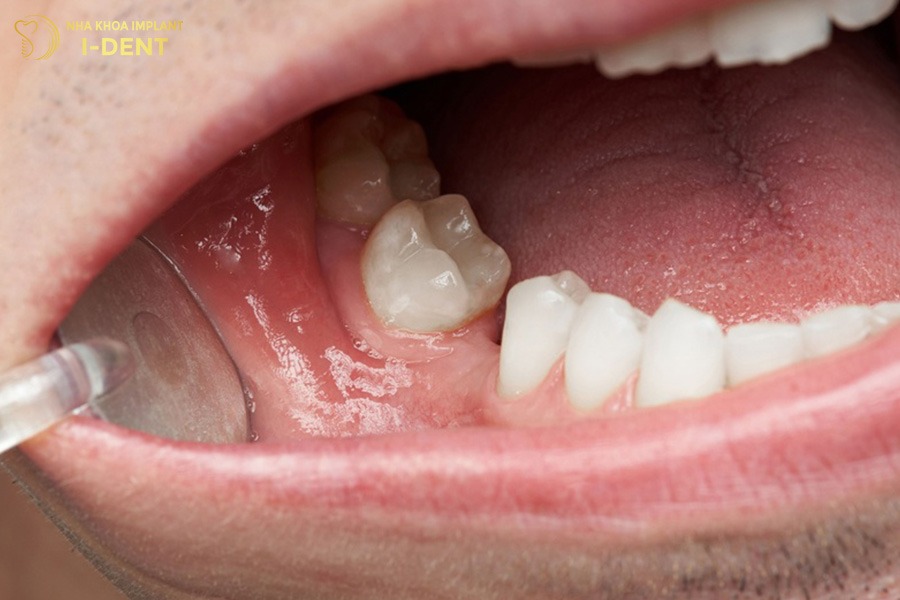

2.3. Lệch khớp cắn, xô lệch các răng còn lại

Khi một chiếc răng mất đi, các răng kế cận có xu hướng nghiêng về khoảng trống hoặc trồi lên, thụt xuống để lấp chỗ trống đó. Sự dịch chuyển này làm cho khớp cắn bị lệch, răng không còn ăn khớp chuẩn như ban đầu. Về lâu dài, tình trạng răng xô lệch khiến việc vệ sinh trở nên khó khăn hơn, tạo điều kiện cho mảng bám và vi khuẩn phát triển.

Khoảng trống mất răng khiến các răng kế cận nghiêng lệch, làm sai khớp cắn.